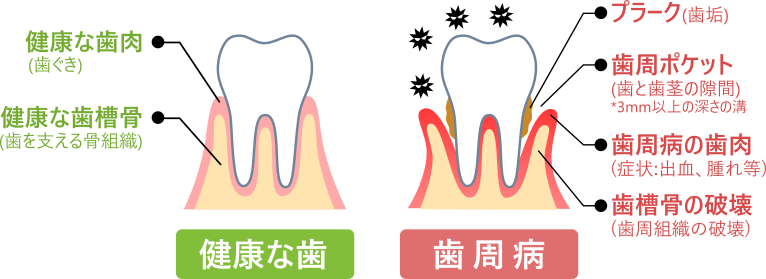

歯周病とは?

歯の病気の代表的なものに、むし歯と歯周病があります。むし歯は〈歯そのもの〉が破壊される病気ですが、歯周病は〈歯を支える周りの組織(歯周組織)〉に起こる病気です。

自分で気づかない軽い歯周病を含めると、38歳以上の成人のうち、5人に4人以上が歯周病にかかっているといわれ、歯周病は歯を失う大きな原因となっています。

歯周病の原因は?

歯周組織は歯肉(歯ぐき)と歯槽骨(歯を支える骨組織)、歯根(歯の根元)をおおうセメント質、歯根と歯槽骨をつなぐ歯根膜からなり、歯を正しい位置にしっかり付着・固定するための強固な構造を備えています。

しかし、歯磨きが不十分で、歯と歯肉の間に細菌が住み着いて歯垢(プラーク)がたまると、そこに炎症が引き起こされます。これが歯周病の始まりです。

歯周病の進行と症状

初めは自覚症状がなく、鏡で見ても気が付きませんが、そのうち歯肉が赤くなったり、腫れたりします。

プラークが石灰化し、自分では取り除きにくくなって歯周病が悪化し、歯と歯肉が付着している部分に隙間(歯周ポケット)ができます。さらに、炎症が歯肉の内部に進行すると、歯根膜や歯槽骨が破壊されて、歯を固定する力がだんだん弱くなります。この状態のまま放っておくと、ついには歯を失うことになります。